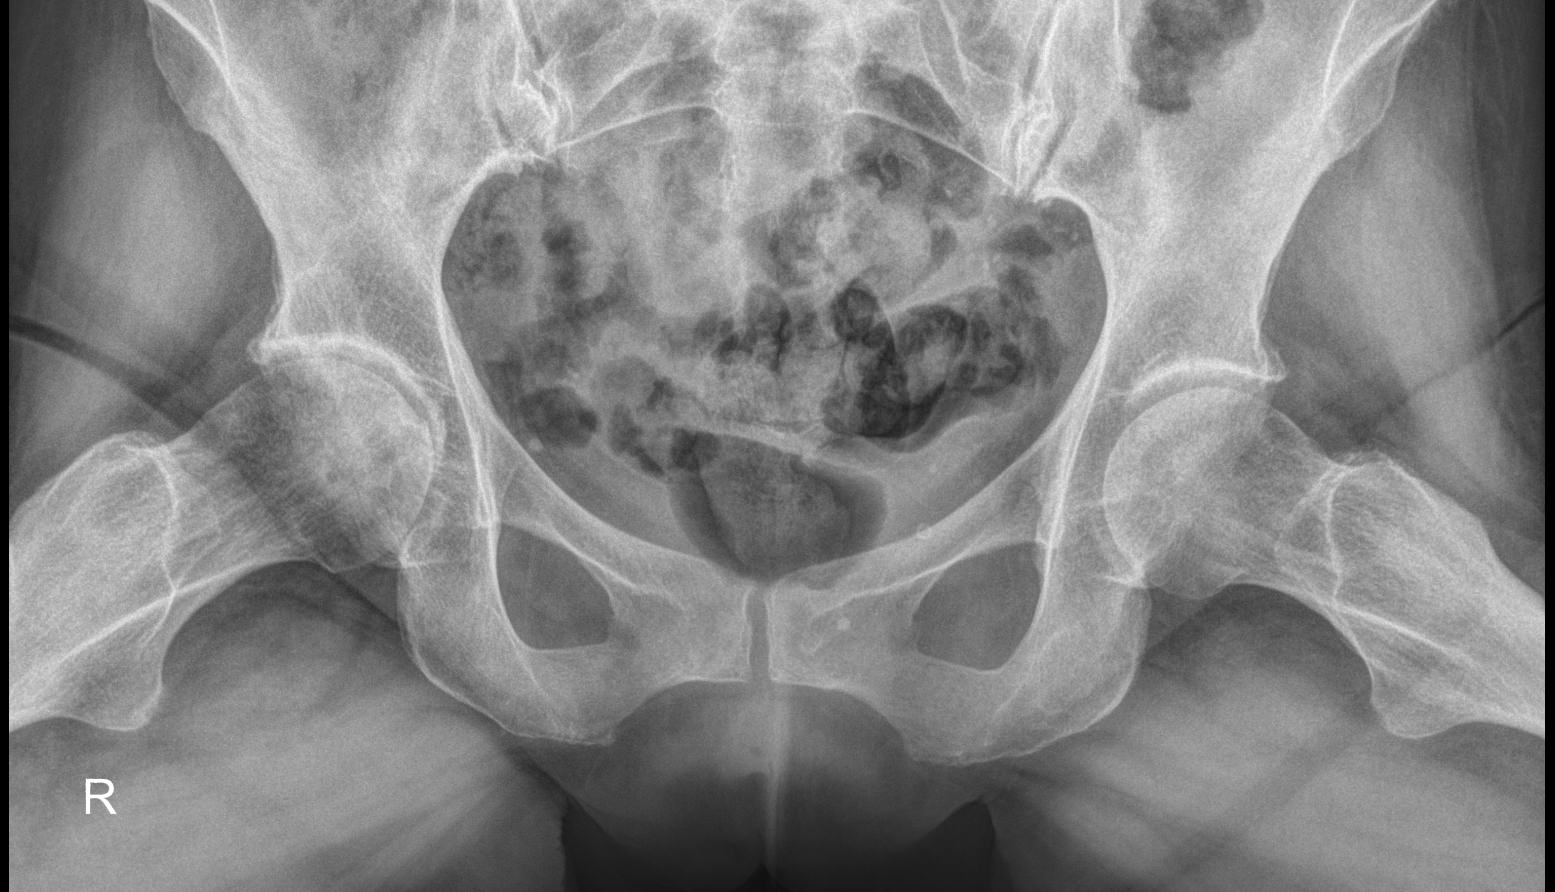

Рентгеновское исследование ― классический метод диагностики костно-суставных патологий. Он основан на способности ионизирующего излучения проходить сквозь ткани и поглощаться ими в большей или меньшей степени. Кости, как наиболее плотные в организме, поглощают большее количество излучения и на классическом негативном снимке выглядят светлыми образованиями. Видны и все изменения в костях и окружающих их структурах.

Рентгеновское исследование в 2 проекциях ― прямой и по Лаунштейну ― входит в список обязательных диагностических процедур при многих болезнях, поражающих тазобедренный сустав. Снимки необходимы как для подбора терапевтического лечения, так и для планирования оперативного вмешательства при эндопротезировании.

Что показывает рентген тазобедренных суставов в прямой проекции и по Лаунштейну

• Контуры костей суставов, линии переломов;

• Соответствие сочленяющихся поверхностей;

• Суставную щель и ее особенности;

• Состояние костной ткани, очаги разрежения;

• Новообразования;

• В положении Лаунштейна особенно четко видна головка бедренной кости и ее изменения.